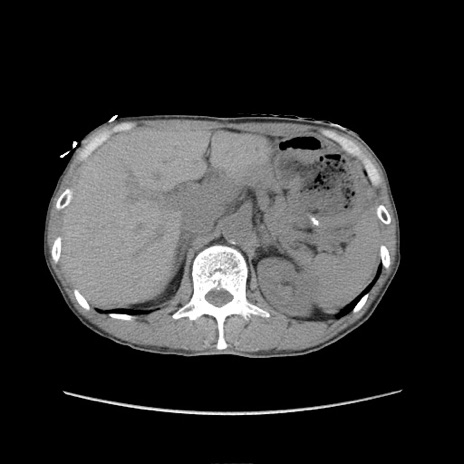

症例11(横断像)

【症例】 60歳代男性

【主訴】 下腹部痛

【現病歴】 本日夜中より下腹部痛の症状認め、受診。

【既往歴】 膀胱癌(膀胱全摘+尿管皮膚瘻術) 、胃癌術後

【身体所見】 BT 35.3℃、PR 58/min、BP 136/98mHg、腹部平坦、軟、腸蠕動音±、ストマ留置あり、左上腹部~正中部に圧痛あり、反跳痛なし。

【データ】WBC 5100、CRP0.01